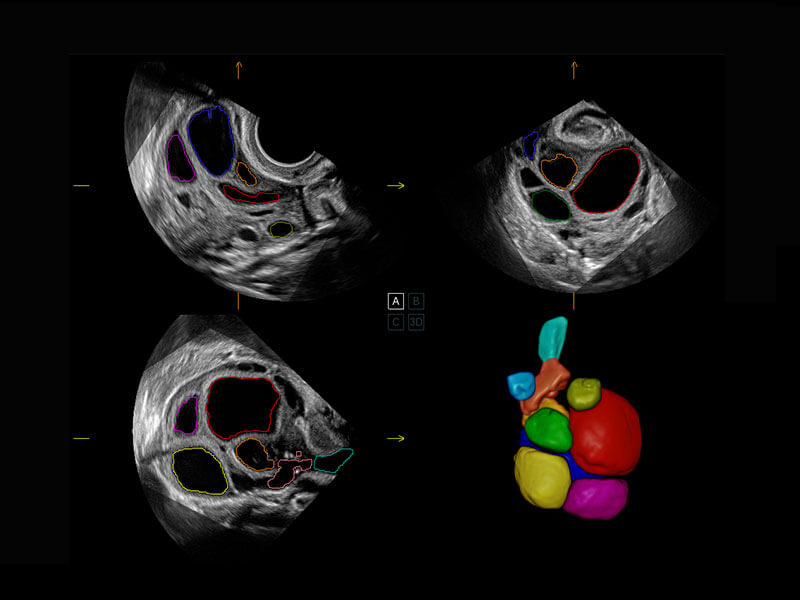

P60搭载一系列胎儿心脏成像技术,实现精细的胎儿心脏评估。

四腔切面

四腔心血流

胎心容积成像